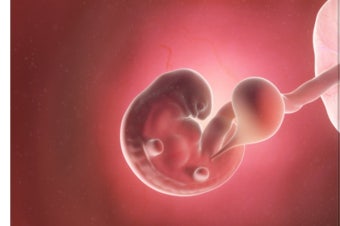

임신 5주차의 태아 발달

5주차의 태아는 아직 매우 작으며 약 1.5~2mm 정도입니다. 이 시기에는 신경관이 형성되며, 뇌와 척수가 점차 구체적인 형태를 갖추게 됩니다. 심장 역시 이 시기부터 박동을 시작하며, 초음파를 통해 심박동이 관찰될 수도 있습니다. 비록 눈에 띄는 외형은 없지만, 태아의 주요 기관들이 형성되는 시기이므로 영양 섭취와 생활습관에 신경 써야 할 중요한 시기입니다.